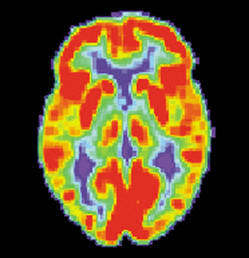

Neuromarketing|Neuromarketing

We see it everyday whether we want it or not ; commercials, health and other warnings on products around us. Marketing is probably one of the areas that are most researched and where unbeliavable...